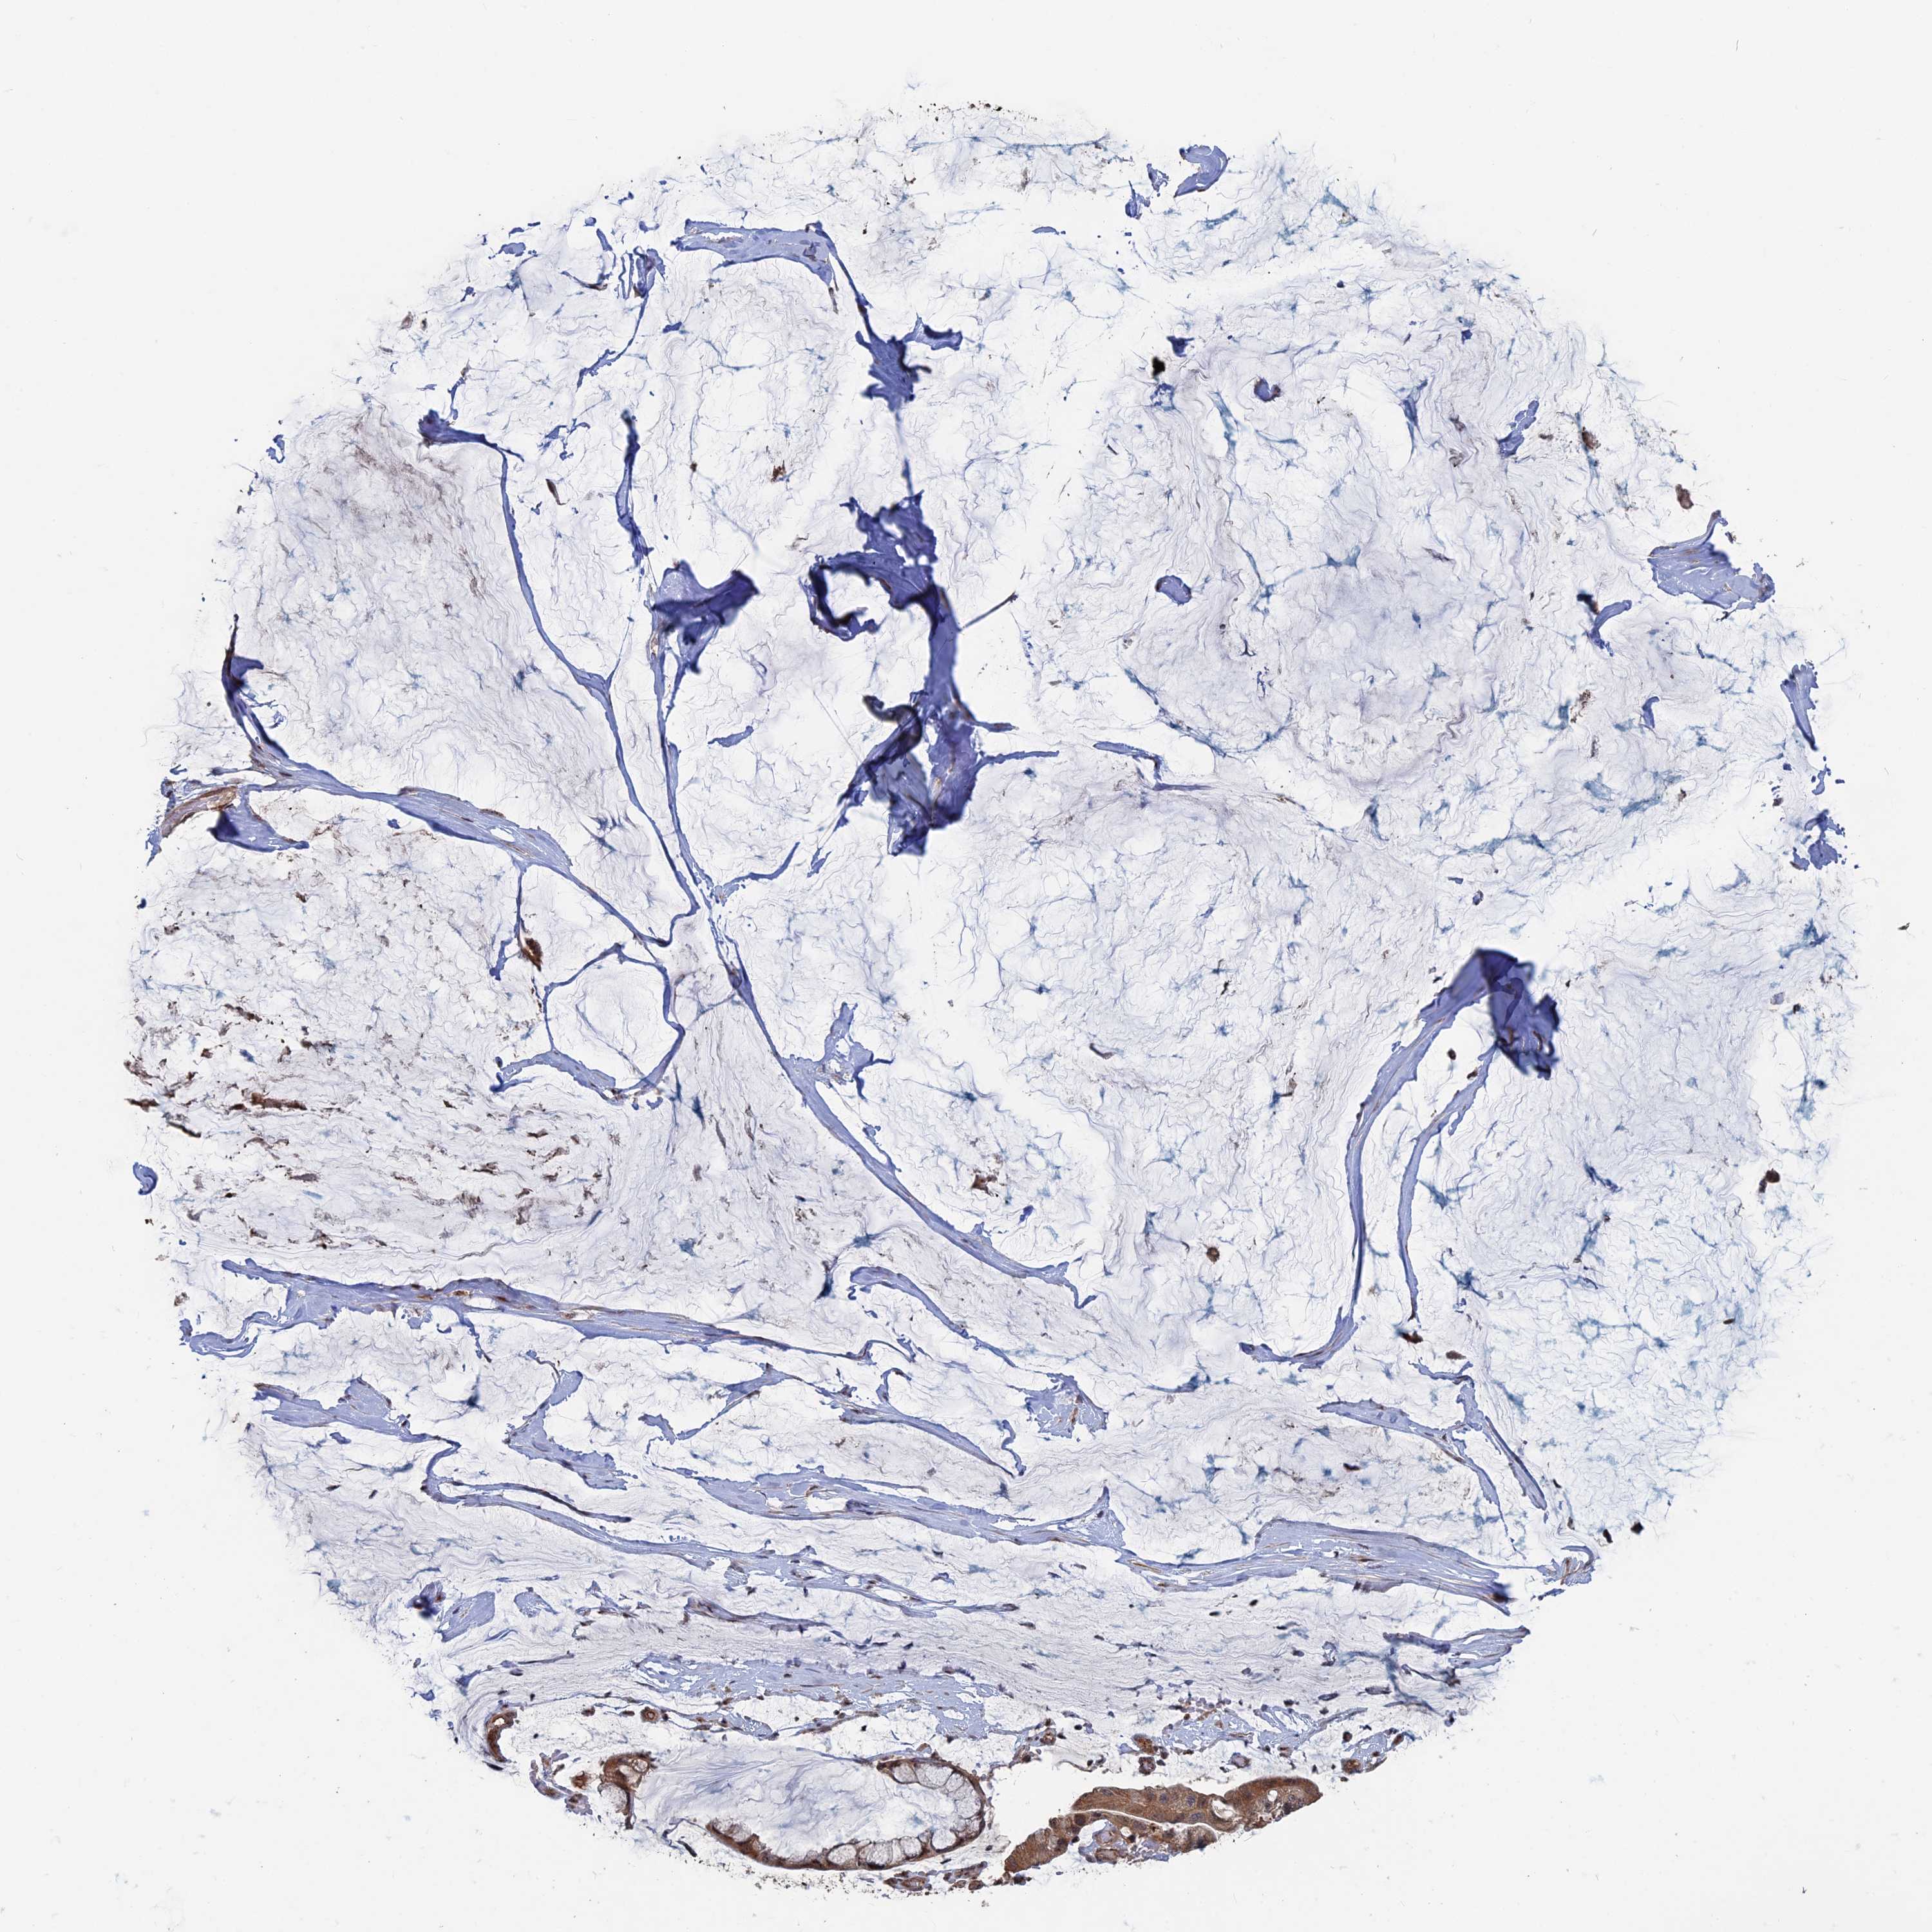

OVARIAN CANCER - Protein expressioni

A mouse-over function shows sample information and annotation data. Click on an image to view it in a full screen mode. Samples can be filtered based on level of antibody staining by selecting one or several of the following categories: high, medium, low and not detected. The assay and annotation is described here.

Note that samples used for immunohistochemistry by the Human Protein Atlas do not correspond to samples in the TCGA dataset.

Antibody stainingi

Antibody staining in the annotated cell types in the current human tissue is reported as not detected, low, medium, or high, based on conventional immunohistochemistry profiling in selected tissues. This score is based on the combination of the staining intensity and fraction of stained cells.

Each image is clickable and will lead to virtual microscopy that enables deeper exploration of all samples and also displays staining intensity scores, fraction scores and subcellular localization as well as patient and tissue information for each sample.

Antibody HPA040946

Staining

High

Medium

Low

Not detected

Intensity

Strong

Moderate

Weak

Negative

Quantity

>75%

75%-25%

<25%

None

Location

Nuclear

Cytoplasmic/membranous

Cytoplasmic/membranous,nuclear

Cystadenocarcinoma, serous, NOS

Carcinoma, endometroid

Cystadenocarcinoma, mucinous, NOS

Carcinoma, NOS